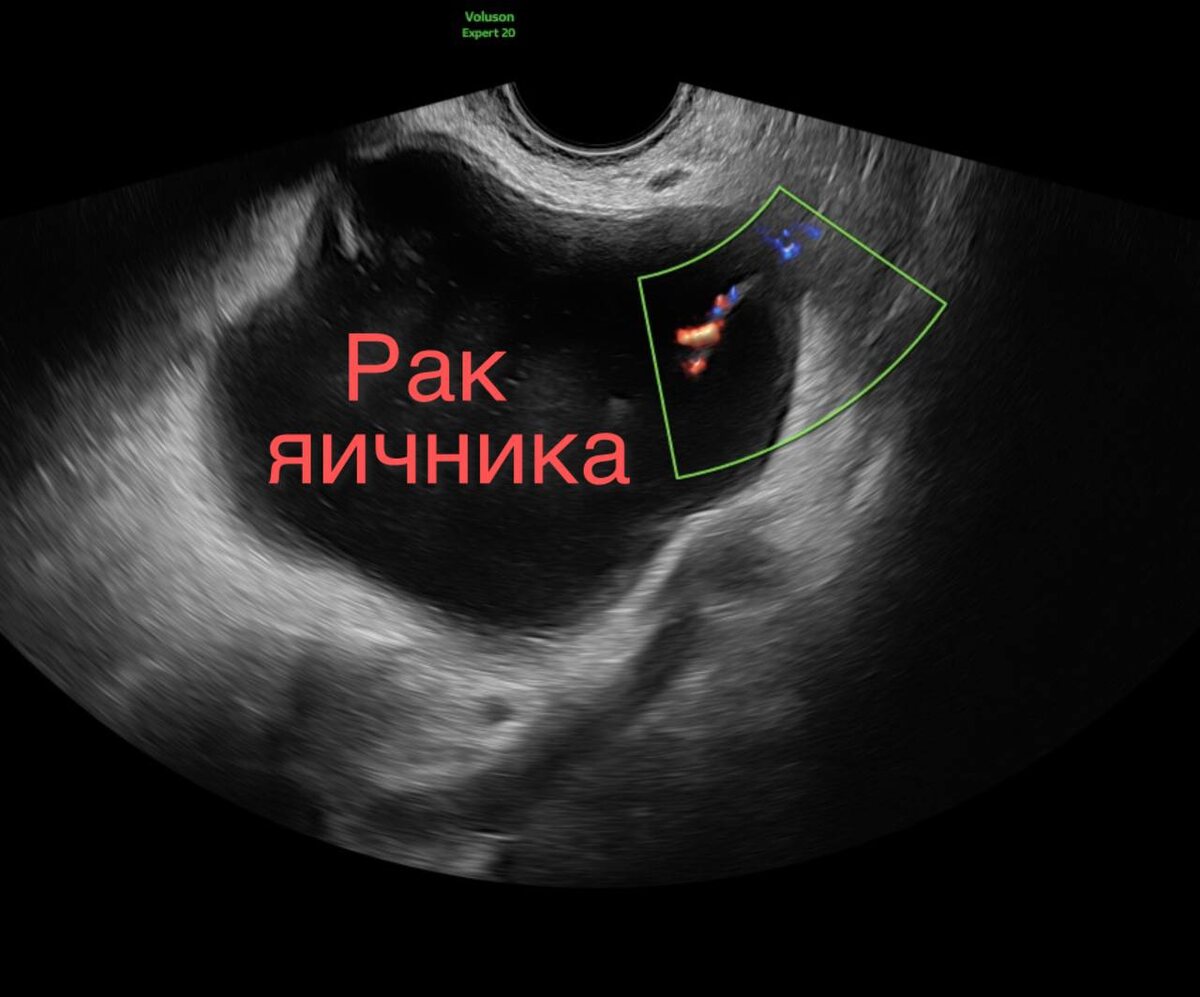

Вот такая была неделя

Вот такая была неделя.